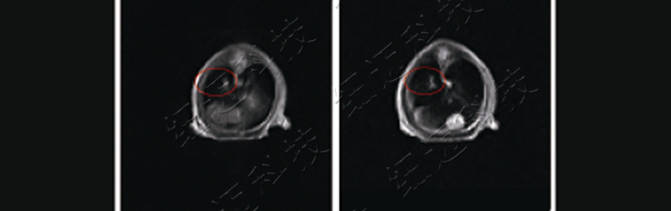

4、裸鼠肺部原位腫瘤位置排查